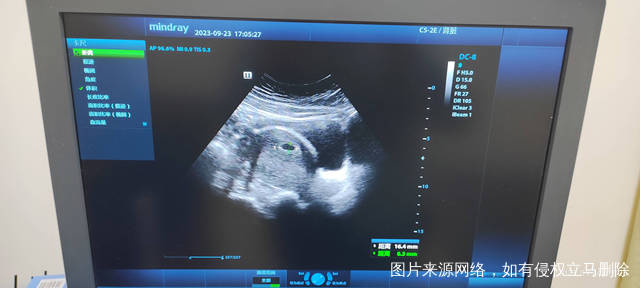

今天是怀孕16周去做了胎心监测还有做了一个B

正常的胎盘附着于子宫体部的前壁、后壁或侧壁,远离宫颈内口。妊娠28周后,胎盘仍附着于子宫下段,其下缘达到或覆盖宫颈内口,位置低于胎儿先露部,称为前置胎盘。你的情况,现在孕周还小,还不能确定是前置胎盘。遵医嘱用药吧!注意休息,观察是否有阴道流血,如果有阴道流血,及时去医院。